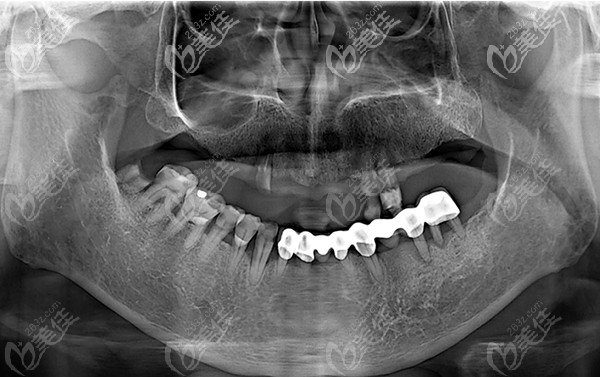

種植前牙片

要不是我這次特地帶他去包頭植諾口腔門診做了一次牙齒檢查,都不知道我爸的牙齒,因牙周炎導(dǎo)致牙齒出現(xiàn)松動掉落,想要修復(fù)已經(jīng)無法保留了,需拔除后做種植牙才能修復(fù)。